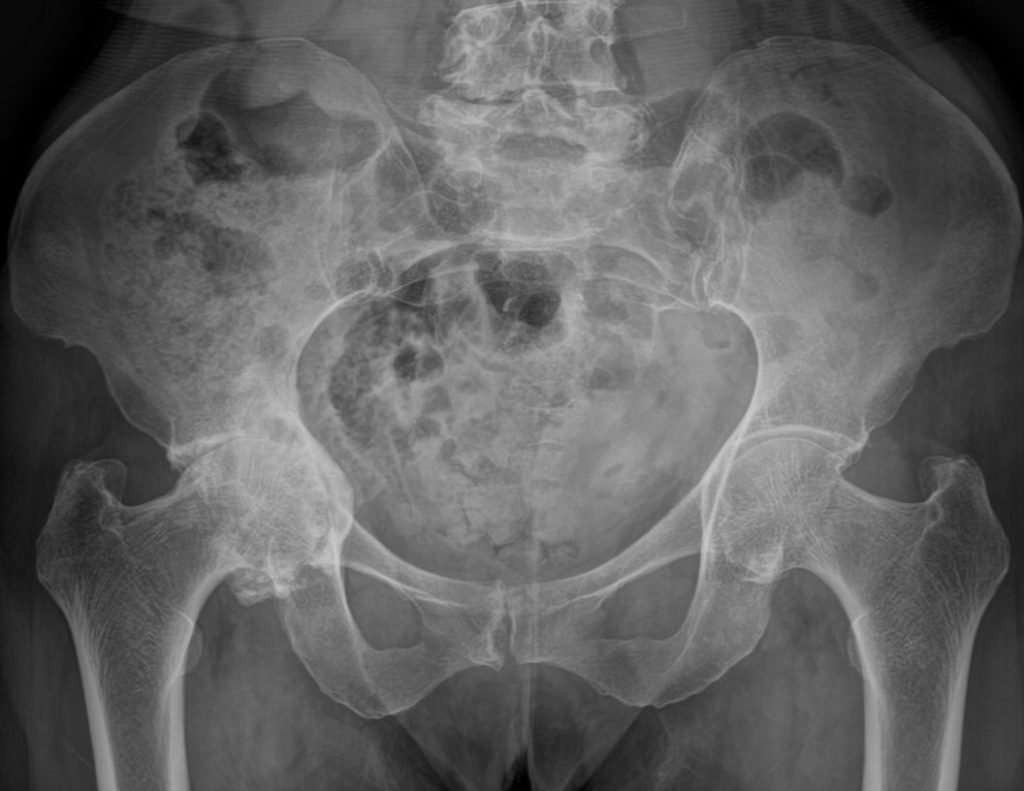

Coxartosi bilaterale

Prima